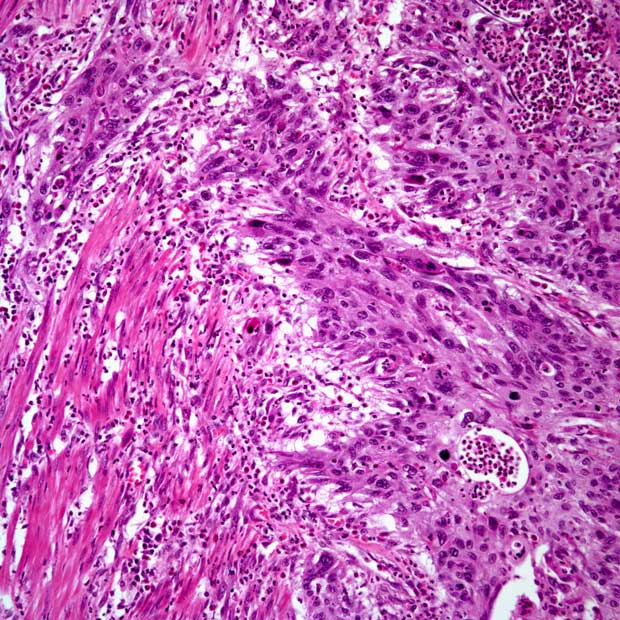

Patients included in the trial had either stage cT2 (68.2%), cT3 (27.3%), or cT4 (4.5%) disease and 68.2% had urothelial carcinoma and 31.8% had a mixed histology. Of the patients evaluated (n = 22), the median age was 74.5 years. All patients were White (100%), 20 were males (90.9%), and 21 (95.5%) were current or former smokers.

Currently, there are no established neoadjuvant treatment options proven to enhance survival for patients diagnosed with MIBC who are ineligible for cisplatin and are undergoing radical cystectomy with pelvic lymph node dissection. Enfortumab vedotin is an antibody-drug conjugate that targets Nectin-4, a protein highly expressed in urothelial cancer. Both alone and in combination with pembrolizumab, enfortumab vedotin improves overall survival compared with chemotherapy in patients with previously treated and untreated locally advanced or metastatic urothelial cancer.